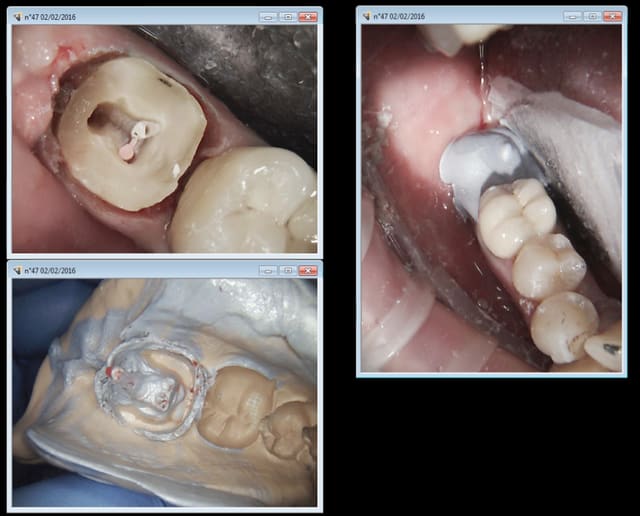

C'est vrai. Le cas suivant était déjà limite mais en plus j'ai pété un sx dans le MV1 et ca s'est terminé en extrac. C'est con les 3 autres je les avais bien. -)

mais ou est la recontitution préendo chicot ?